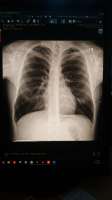

Аноны, видите ли вы здесь рак легких?